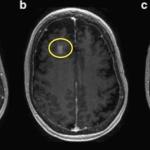

Senator John McCain’s office just released a statement from the Mayo Clinic Hospital in Phoenix detailing his newly diagnosed Glio